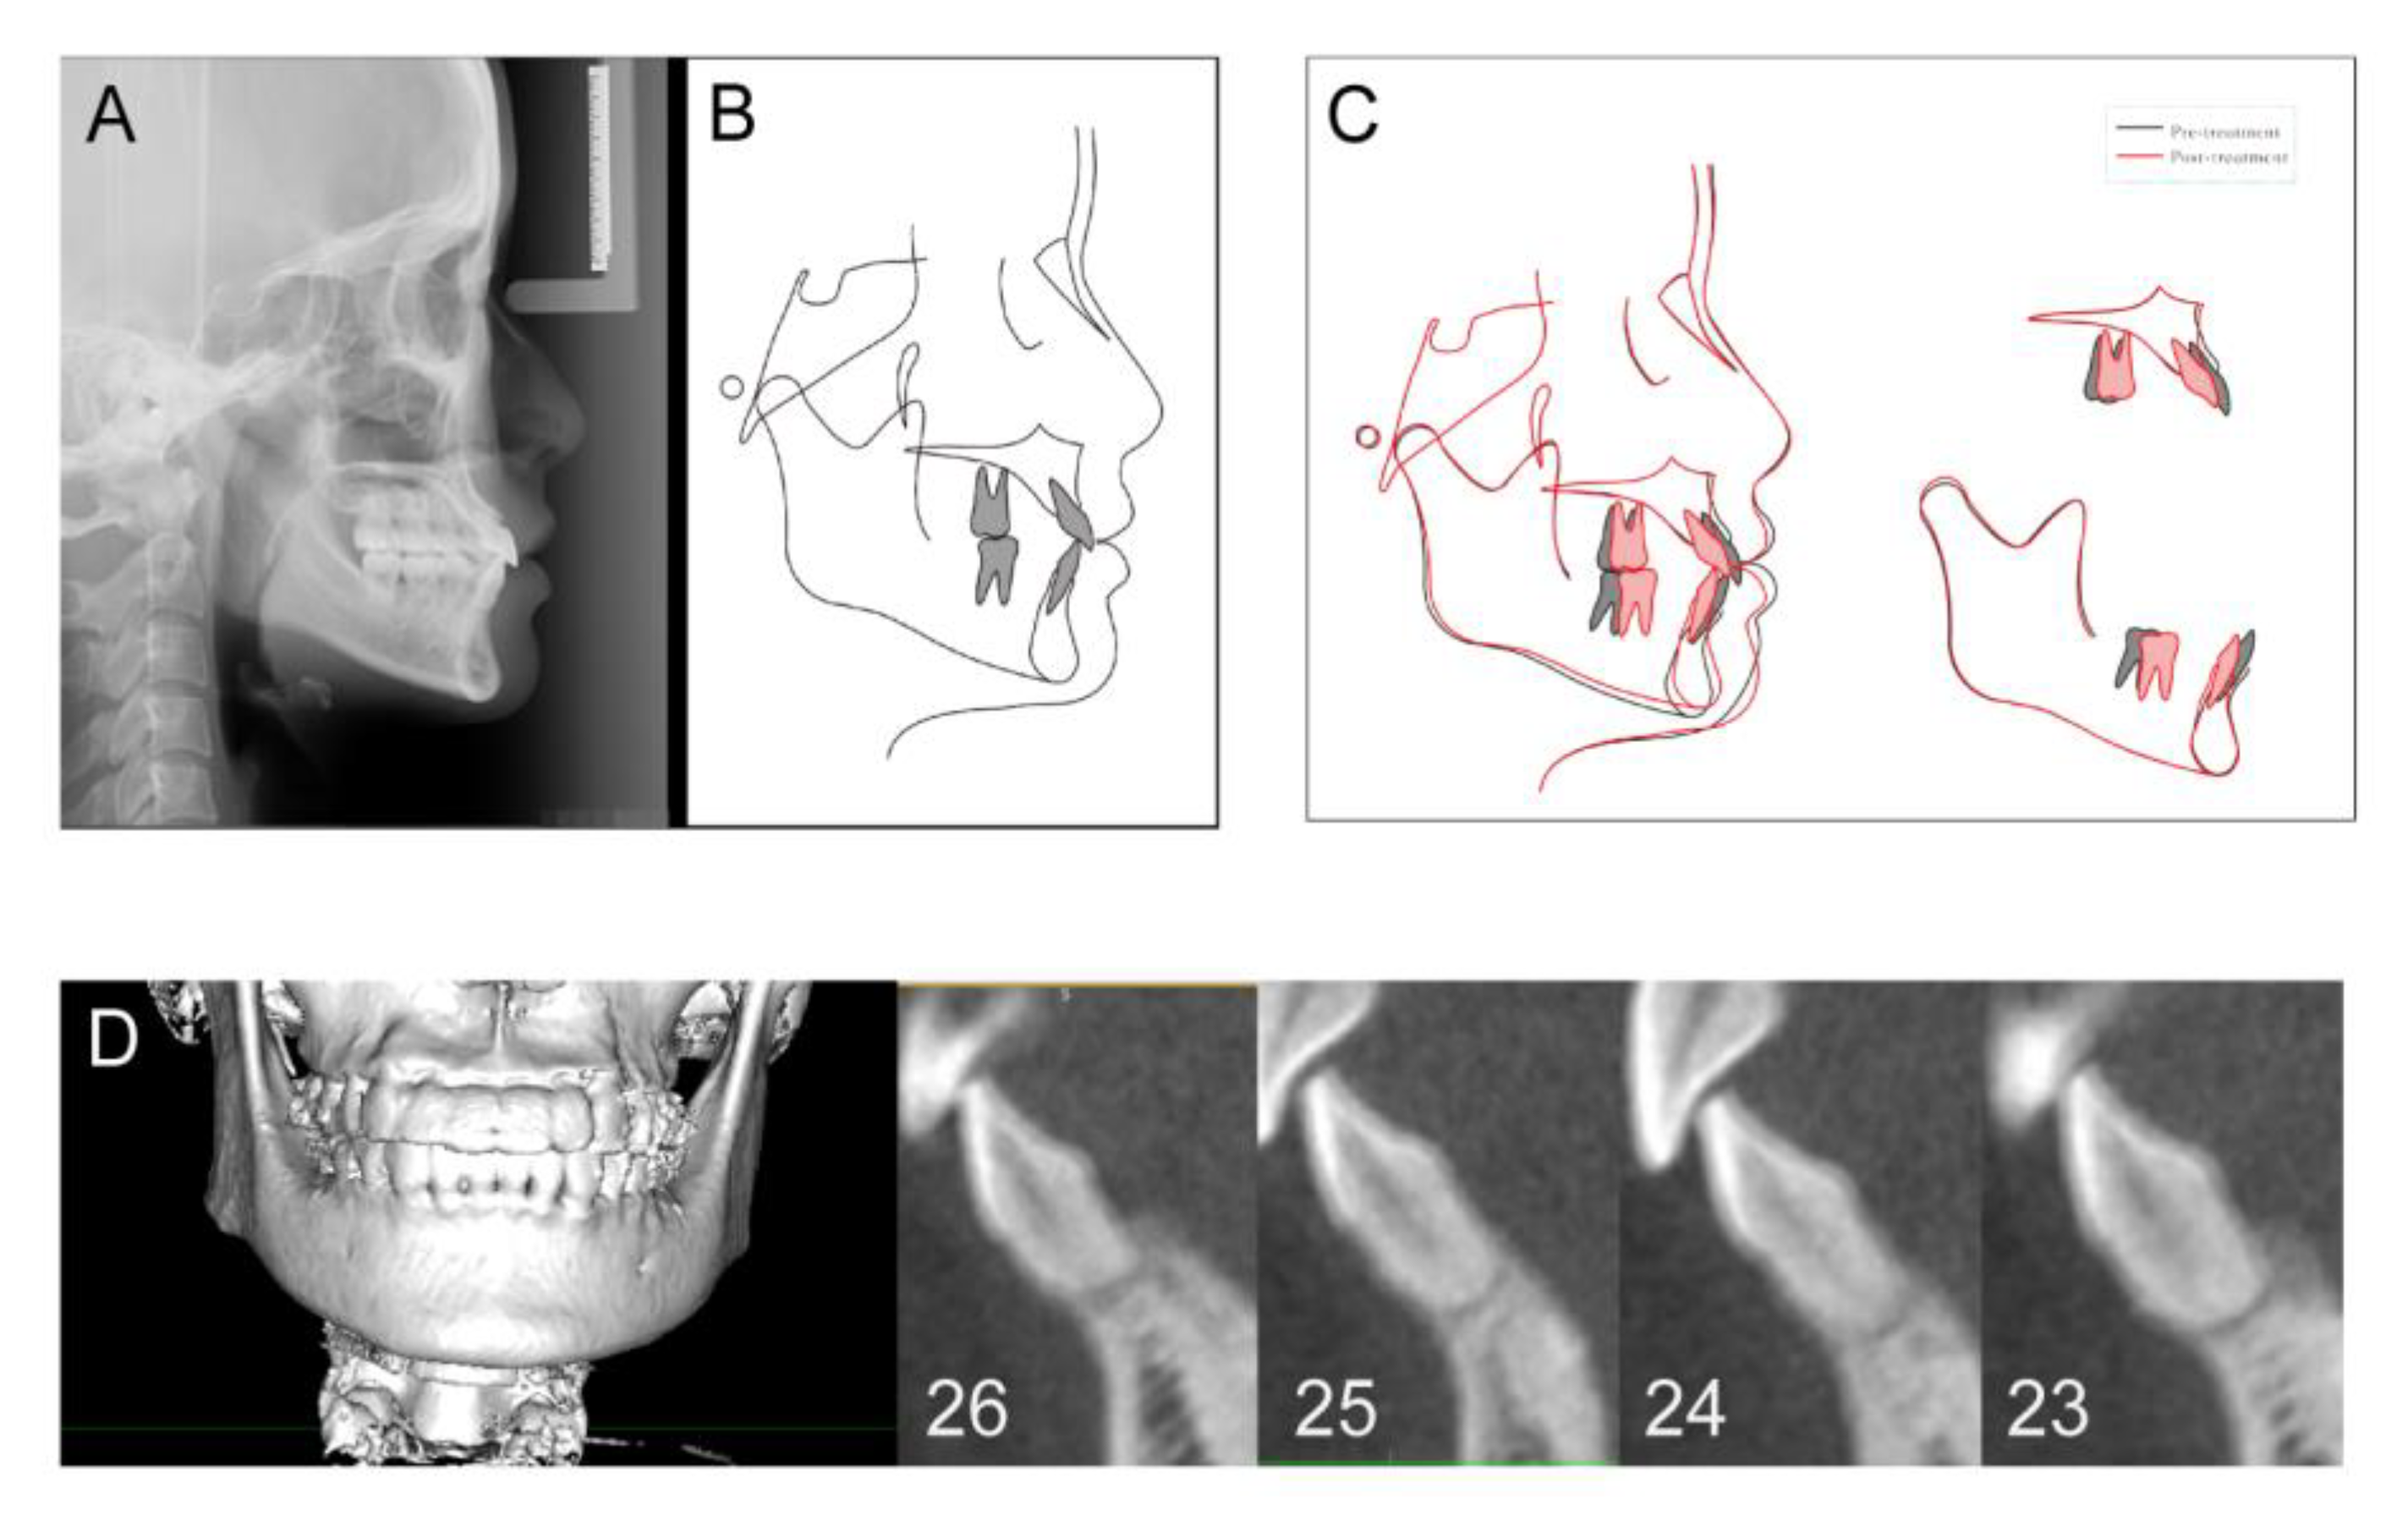

| Measurement | Normal (Standard Deviation) | Pretreatment | Posttreatment | Difference |

|---|---|---|---|---|

| SNA (°) | 83.1 (2.7) | 82.0 | 81.9 | −0.1 |

| SNB (°) | 80.3 (2.6) | 79.2 | 80.0 | 0.8 |

| ANB (°) | 2.7 (1.8) | 2.8 | 1.9 | −0.9 |

| UI—SN (°) | 103.4 (5.5) | 105.8 | 108.4 | 2.6 |

| LI—MP (°) | 96.3 (5.4) | 105.2 | 90.7 | −14.5 |

| UI-LI (°) | 129.1 (7.1) | 118.1 | 131.1 | 13 |

| MP—SN (°) | 32.6 (6.9) | 30.9 | 29.8 | −1.1 |

| MP—FH (°) | 25.5 (4.8) | 26.1 | 25.1 | −1.0 |

| Wits (mm) | −1 (1) | −0.8 | −1 | 0.2 |

| PP-OP (°) | 10 (4) | 7.3 | 5.1 | −2.2 |

| P-A Face Height (%) | 65 (4) | 67.5 | 68.4 | 0.9 |

| Y-Axis (°) | 67 (5.5) | 68.2° | 66.7 | −1.5 |

| UL-E (mm) | −1.6 (1.5) | −0.1 | −1.8 | −1.7 |

| LL-E (mm) | −0.2 (1.9) | 4.1 | −0.6 | −4.7 |

| Tooth | 26 | 25 | 24 | 23 | Mean ± SD |

|---|---|---|---|---|---|

| Lingual (mm2) | 1.49 | 1.74 | 1.82 | 1.09 | 1.54 ± 0.33 |

| Labial (mm2) | 0.68 | 1.86 | 0.68 | 0.94 | 1.04 ± 0.56 |

| Coronal (mm) | 0.40 | 0.63 | 0.30 | 2.11 | 0.86 ± 0.84 |

| Middle (mm) | 1.14 | 0.88 | 0.76 | 2.22 | 1.25 ± 0.67 |

| Apical (mm) | 0.26 | 1.14 | 0.31 | 1.87 | 0.72 ± 0.77 |